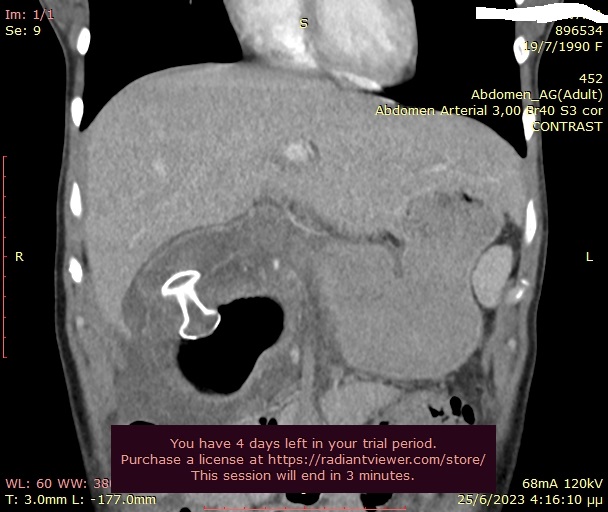

• Σε ασθενείς με περιπαγκρεατικές συλλογές δηλ. περιχαρακωμένες νεκρώσεις (walled-off necrosis) ή ψευδοκύστεις μετά από επεισόδιο οξείας παγκρεατίτιδας. Σε αυτούς γίνεται ενδοσκοπική παροχέτευση των συλλογών με τοποθέτηση πλαστικών ή μεταλλικών stent (LAMS, lumen apposing stents) μέσα από τον στόμαχο ή το δωδεκαδάκτυλο. Έτσι αποφεύγονται βαρύτατα χειρουργεία.

• Σε βεβαρημένους ασθενείς με οξεία χολοκυστίτιδα που δεν μπορούν να χειρουργηθούν λόγω υψηλής συ-νοσηρότητας και αυξημένου κινδύνου θανάτου. Σε αυτούς τοποθετείται μεταλλικό, πλήρως καλυμμένο stent (LAMS) διαγαστρικά, με την καθοδήγηση του ενδοσκοπικού υπερήχου και παροχετεύεται η χολή στον στόμαχο.